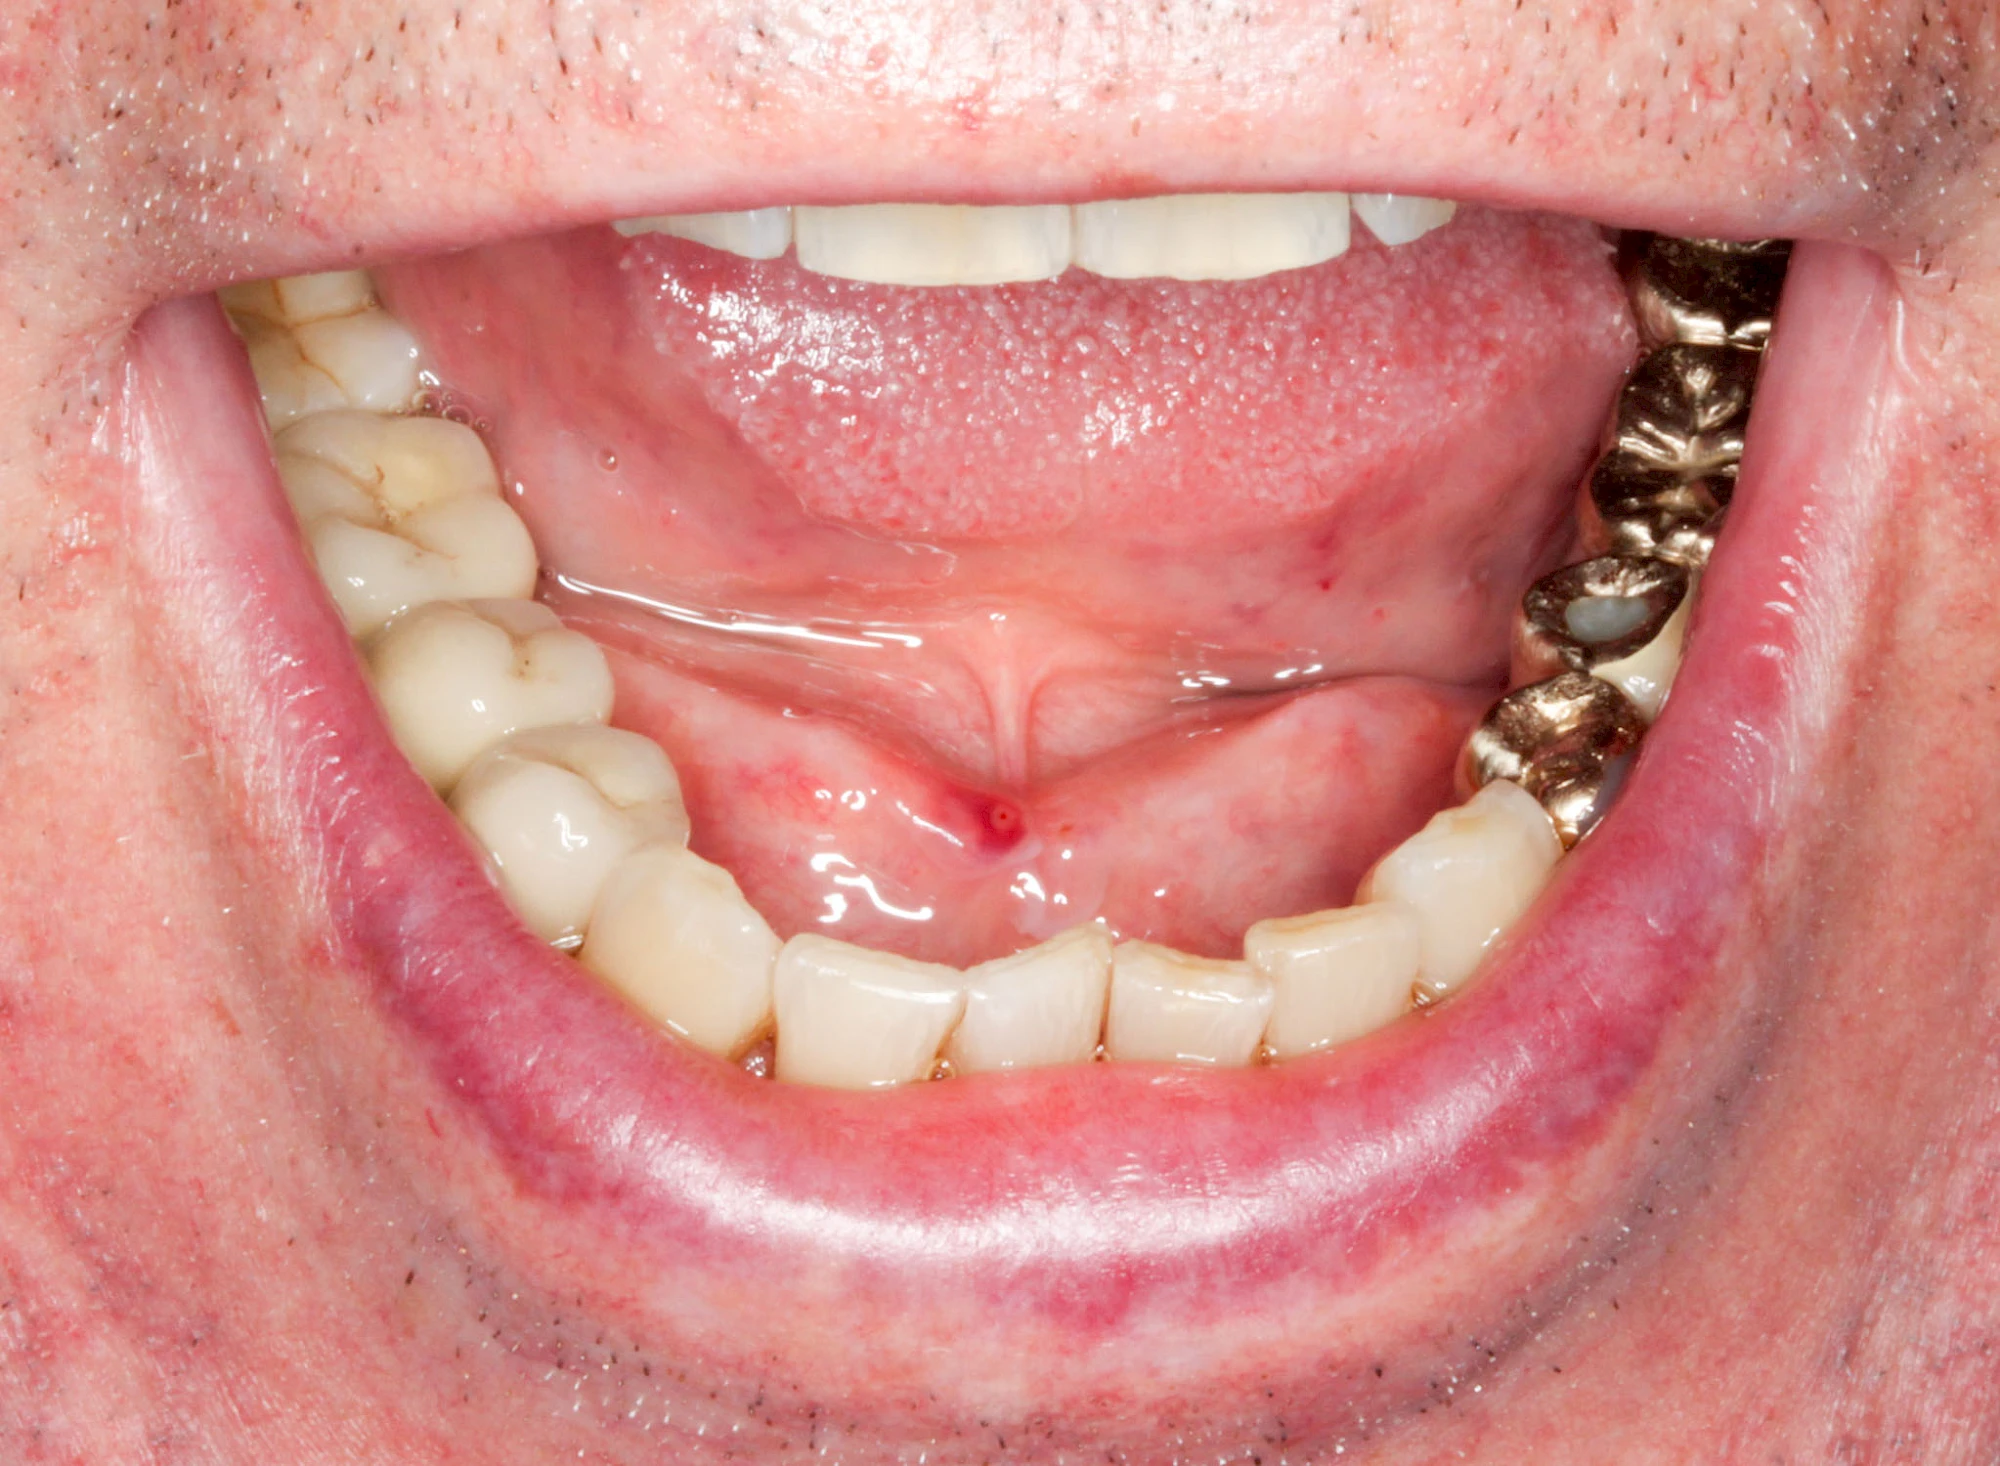

Speicheldrüsenzyste

Eine Speicheldrüsenzyste (Speicheldrüsenretentionszsyte) kann als Schwellung oder Auftreibung meist im Bereich der größeren Ausführungsgängen auffallen, wenn z. B. ein Speichelstein den Speichelfluss behindert. Vor allem bei den Mahlzeiten, wenn der Speichelfluss angeregt wird, nimmt die Auftreibung oder Schwellung schmerzhaft weiter zu. In der Regel ist die Unterkieferspeicheldrüse (Glandula sublinugalis) betroffen. Man spricht dann auch von einer Frosch- bzw. Fröschleingeschwulst (Ranula). Bringt sanftes Massieren der Schwellung bzw. Auftreibung keine Verbesserung, sollte ein Arzt oder Zahnarzt hinzugezogen werden